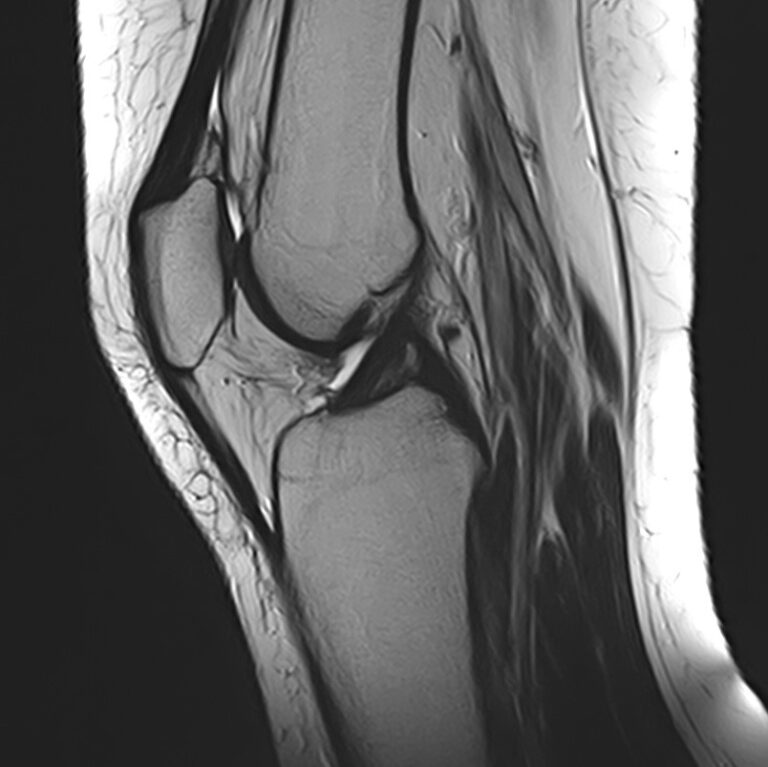

Магнитно-резонансная томография является высокоинформативным методом выявления причин возникновения заболеваний коленного сустава. В клинике «Доступная медицина» диагностика осуществляется на новейшем высокопольном томографе закрытого типа TOSHIBA VANTAGE TITAN 1,5 Тесла, обеспечивающем высочайшее качество изображений исследуемой зоны.

Томограф позволяет детально визуализировать как костные структуры колена, так и окружающие мягкие ткани данной анатомической области, включая мышцы, связки, нервные сплетение, сосуды.